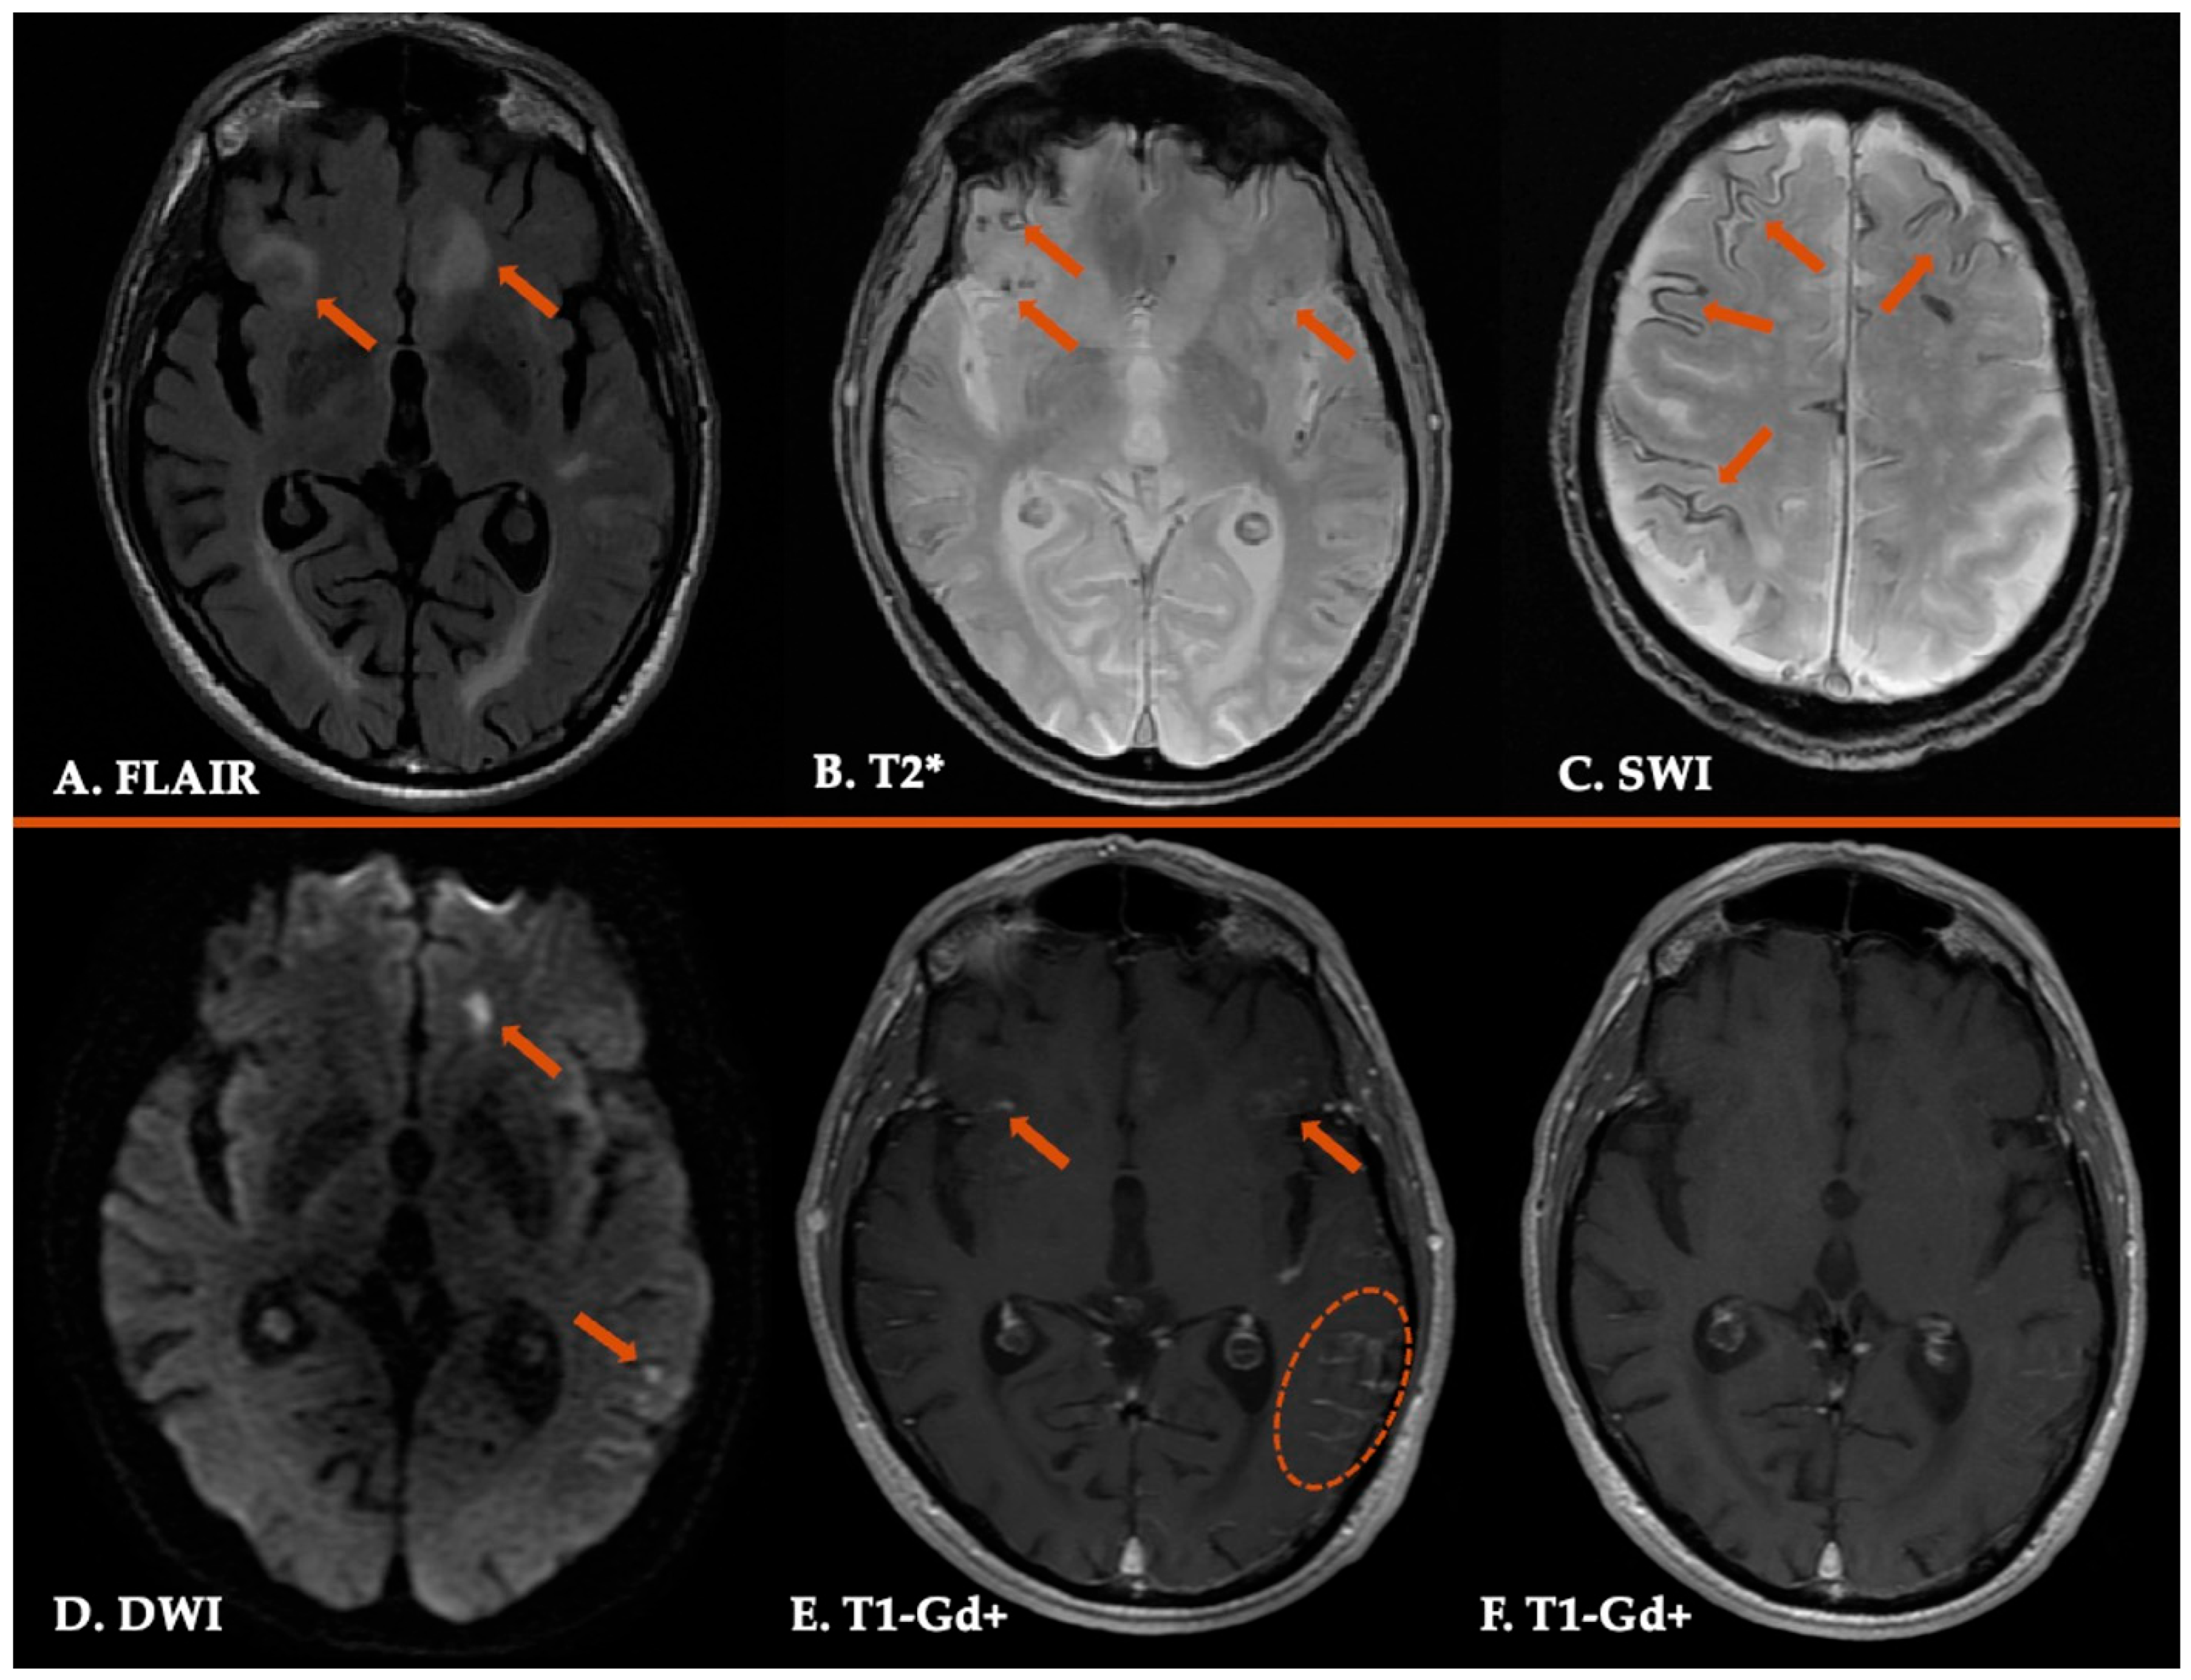

| 3. Probable CAA | Clinical data and MRI demonstrating the following: • Age ≥ 50 years • Presentation with spontaneous ICH, TFNEs, or CI/Dementia • ≥2 of the following strictly lobar hemorrhagic lesions on T2*-weighted MRI, in any combination: ICH, CMB, cSS/cSAH foci OR • 1 lobar hemorrhagic lesion + 1 white matter feature (Severe CSO-PVS or WMH-MS) • Absence of any deep hemorrhagic lesions (ICH, CMB) on T2*weighted-MRI • Absence of other cause of hemorrhagic lesions * • Hemorrhagic lesion in cerebellum not counted as either lobar or deep hemorrhagic lesion |

| 4. Possible CAA | Clinical data and MRI demonstrating the following: • Age ≥ 50 years • Presentation with spontaneous ICH, TFNEs, or CI/Dementia • Absence of other cause of hemorrhage * • 1 strictly lobar hemorrhagic lesion on T2*-weighted MRI: ICH, CMB, cSS/cSAH focus OR • 1 white matter feature (Severe CSO-PVS or WMH-MS) • Absence of any deep hemorrhagic lesions (ICH, CMB) on T2*-weighted MRI • Absence of other cause of hemorrhagic lesions * • Hemorrhagic lesion in cerebellum not counted as either lobar or deep hemorrhagic lesion |

| 2. Probable CAA-ri | 1. Age > 40 y 2. Presence of ≥1 of the following clinical features: headache, decrease in consciousness, behavioral change, or focal neurological signs and seizures; the presentation is not directly attributable to an acute ICH 3. MRI shows unifocal or multifocal WMH lesions (corticosubcortical or deep) that are asymmetric and extend to the immediately subcortical white matter; the asymmetry is not due to past ICH 4. Presence of ≥1 of the following corticosubcortical hemorrhagic lesions: cerebral macrobleed, cerebral microbleed, or cortical superficial siderosis 5. Absence of neoplastic, infectious, or other cause |

| 3. Possible CAA-ri | 1. Age ≥ 40 y 2. Presence of ≥1 of the following clinical features: headache, decrease in consciousness, behavioral change, or focal neurological signs and seizures; the presentation is not directly attributable to an acute ICH 3. MRI shows WMH lesions that extend to the immediately subcortical white matter 4. Presence of ≥1 of the following corticosubcortical hemorrhagic lesions: cerebral macrobleed, cerebral microbleed, or cortical superficial siderosis 5. Absence of neoplastic, infectious, or other cause |